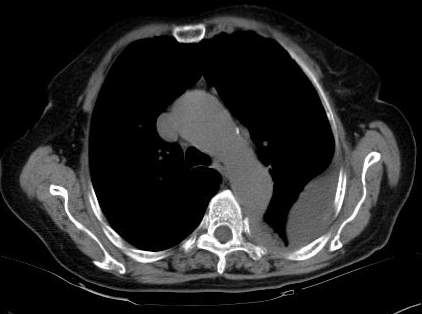

请上传纵隔窗。目前还是支技包裹性积液(明显梭形),即使是间皮瘤并积液也少梭形的。

标题: 回复:病历讨论,胸膜间皮瘤?(是同一个病人吧)

从图片看,包裹性积液好象更合理,梭形,ct值3-5hu(在哪看到的?);胸膜间皮瘤如此规则,不多见。

左侧背部胸膜肥厚,伴包裹性积液,不考虑间皮瘤.

同意以上各位的高见,首先考虑包裹性积液,1.胸膜间皮瘤积液量一般较大,以游离性积液更为常见,2.可以看到增厚的胸膜结节